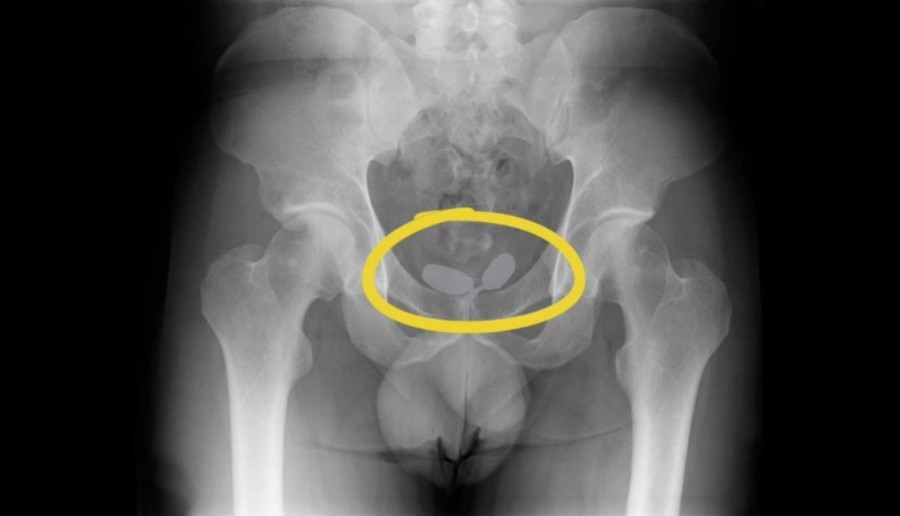

Yapılan röntgen muayenesinde, Alman uyruklu kadının cinsel organında prezervatifler içerisine gizlenmiş uyuşturucular ele geçirildi. Diğer Alman yabancı uyruklu erkeğin ise uyuşturucuları anüsüne gizlediği belirlendi. Yapılan muayene sonrası; 21,19 gram eroin, 12,70 gram kokain, 7,76 gram amfetamin, 7 adet sentetik ecza ele geçirildi.